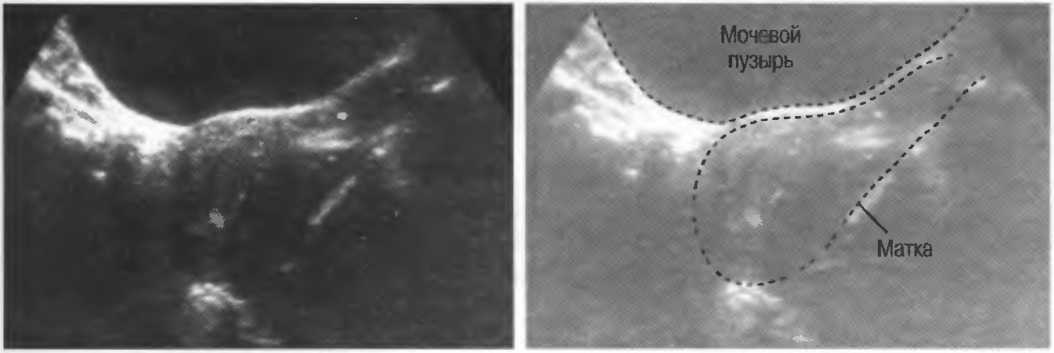

Рис.9. Поперечные срезы увеличенной матки на различном фоне.